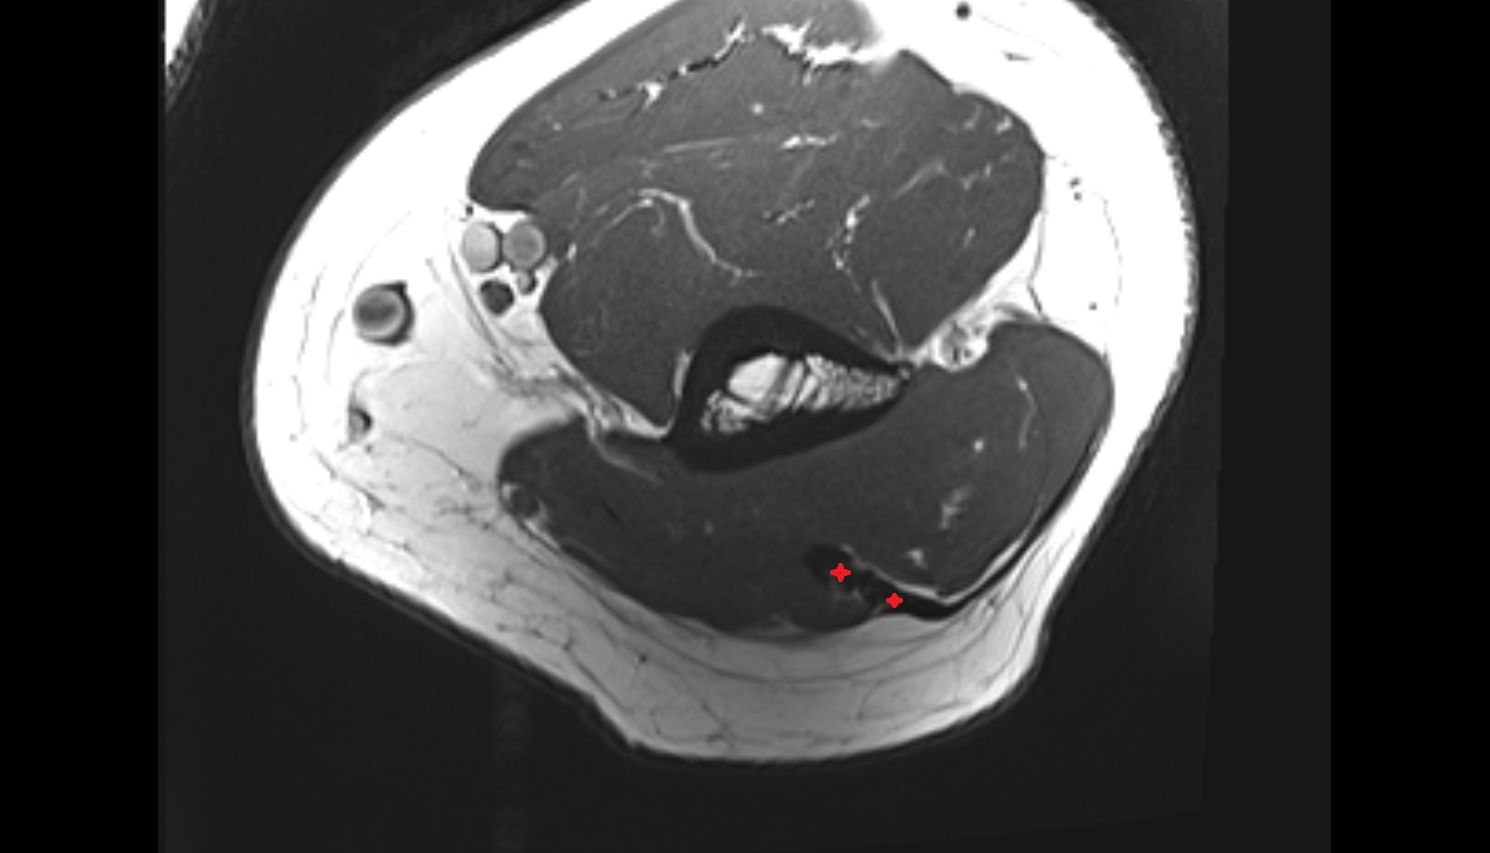

- Medial meniscus

- Lateral meniscus